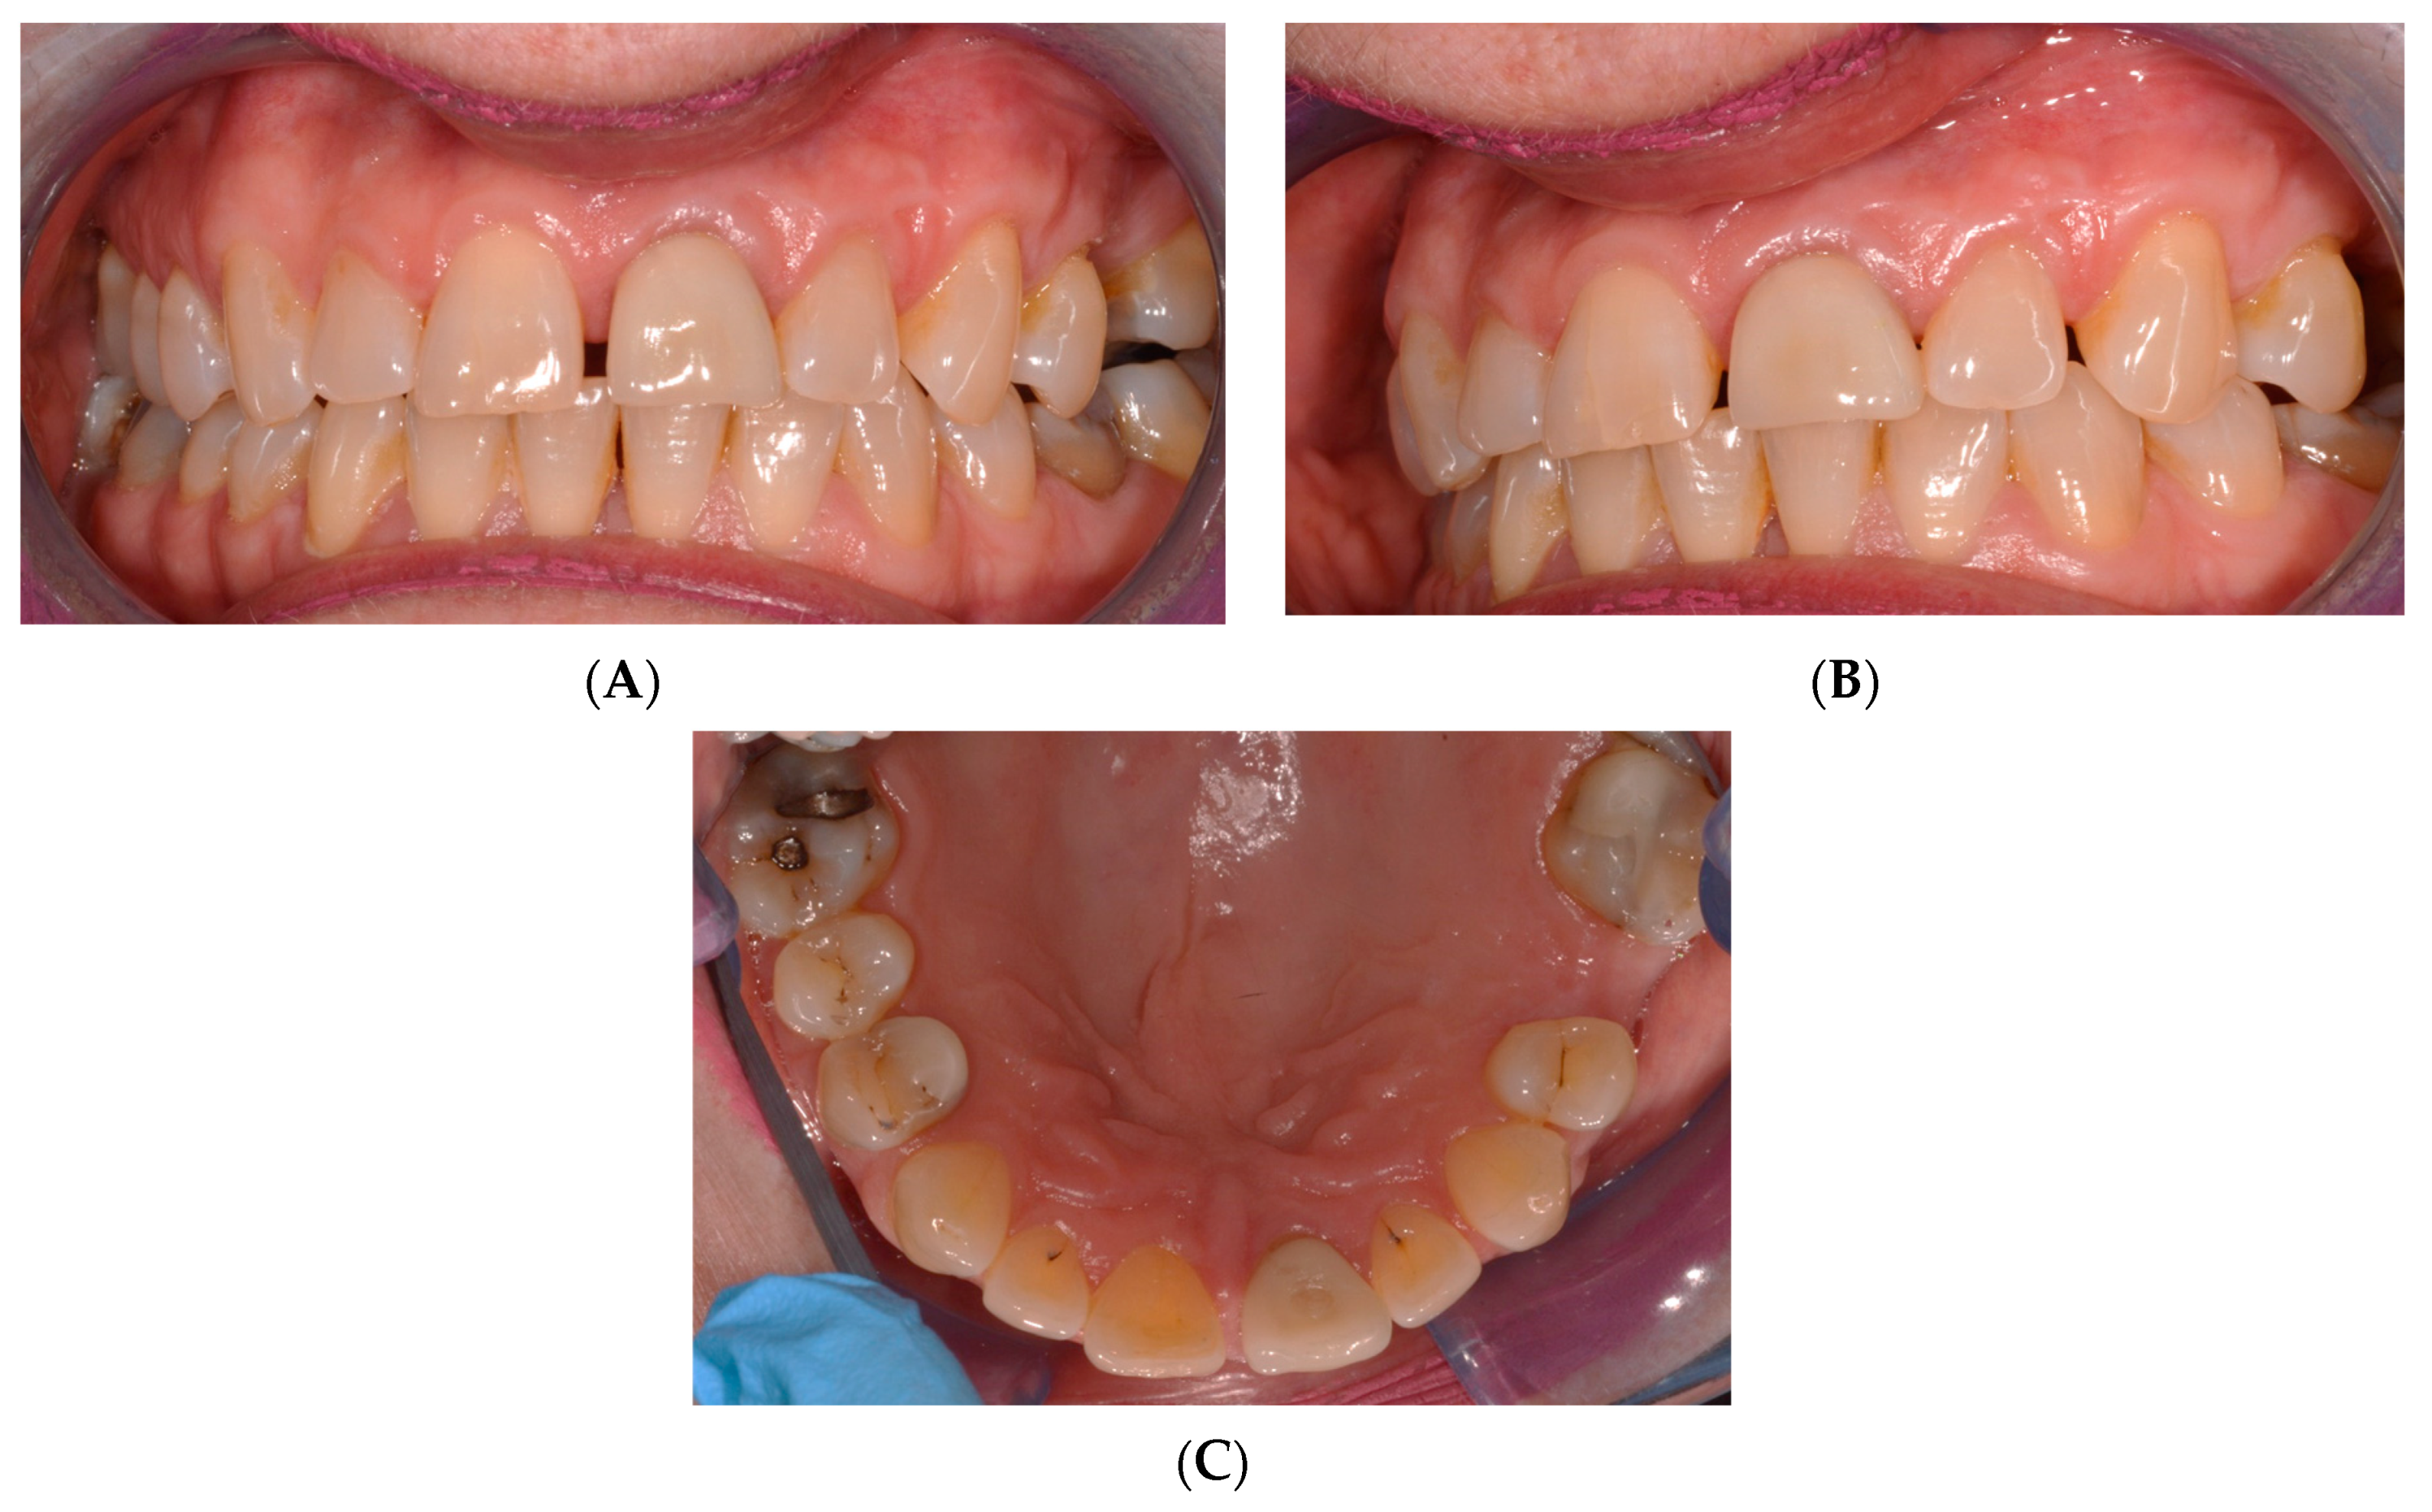

2. Case Presentation

2.1. Chief Complaints History and Clinical Findings

2.2. Delivery of Treatment